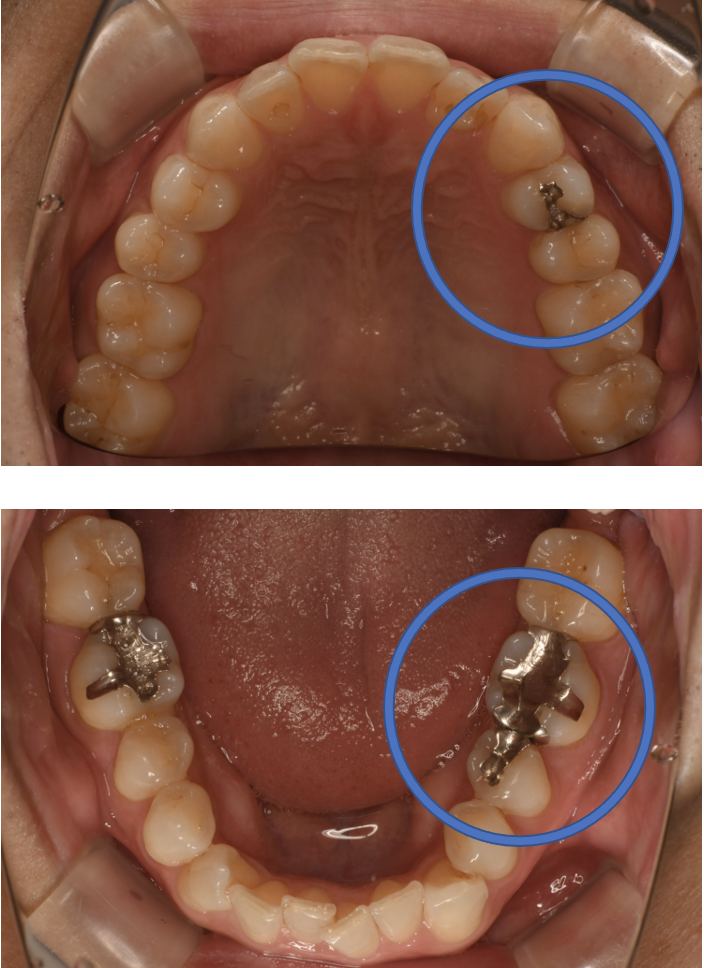

E-max In 2 + フルジルコニアCr No.27

Before

After

| 治療方法 | セラミックインレー(E-MAX In)、ジルコニアCr 虫歯などで失った歯質を天然歯と同じ色・質感のセラミックで補う治療法です。金属を使用する治療と比べて、審美性だけではなく、耐久性や体の負担が少ないという面でも優れていると注目されています。従来のセラミックと比べて天然歯と同程度の強度であり、耐久性が高くなっています。どのくらいもつかは使用状況や部位、メンテナンスの有無などによって大きく変わってきます。透明感があり、キレイで自然な色調を表現できます。歯と分子レベルの化学結合によって吸着するため隙間ができることが少なく、虫歯にもなりにくいと言われています。 そして、金属アレルギーのリスクがありません。 |

| 治療のデメリット | 変色がなく、耐久性が高い治療ですが、歯周病や二次虫歯を予防する為には歯科医院でのお口のクリーニングが大切です。強度が強いといっても、セラミックですから割れる可能性はあります。自由診療の選択肢なので、保険治療と比較して高額になります。 |

| 費用 | ¥69,000×2本、¥89,000=¥267,000 |

| 通院回数 | 1ヶ月〜6ヶ月 |

| 備考 | 院長より 銀の詰め物の内部に虫歯が進行してしまっていたケースです。上の詰め物、下の詰め物は元々の金属が詰められていた部分は狭かったので、 虫歯を除去して詰め物でやり直すことが可能でしたが、奥歯はもともとの金属が大きく内部でも虫歯が進行していたので、薄くなった残存歯質を守る為にも被せる治療になりました。 |